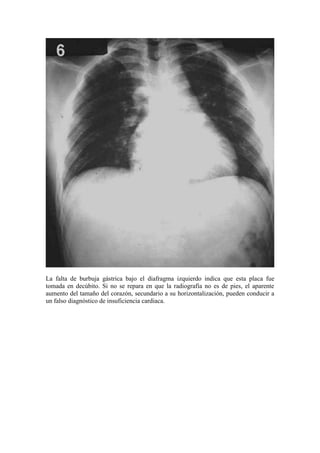

La falta de burbuja gástrica bajo el diafragma izquierdo indica que esta placa fue

tomada en decúbito. Si no se repara en que la radiografía no es de pies, el aparente

aumento del tamaño del corazón, secundario a su horizontalización, pueden conducir a

un falso diagnóstico de insuficiencia cardiaca.